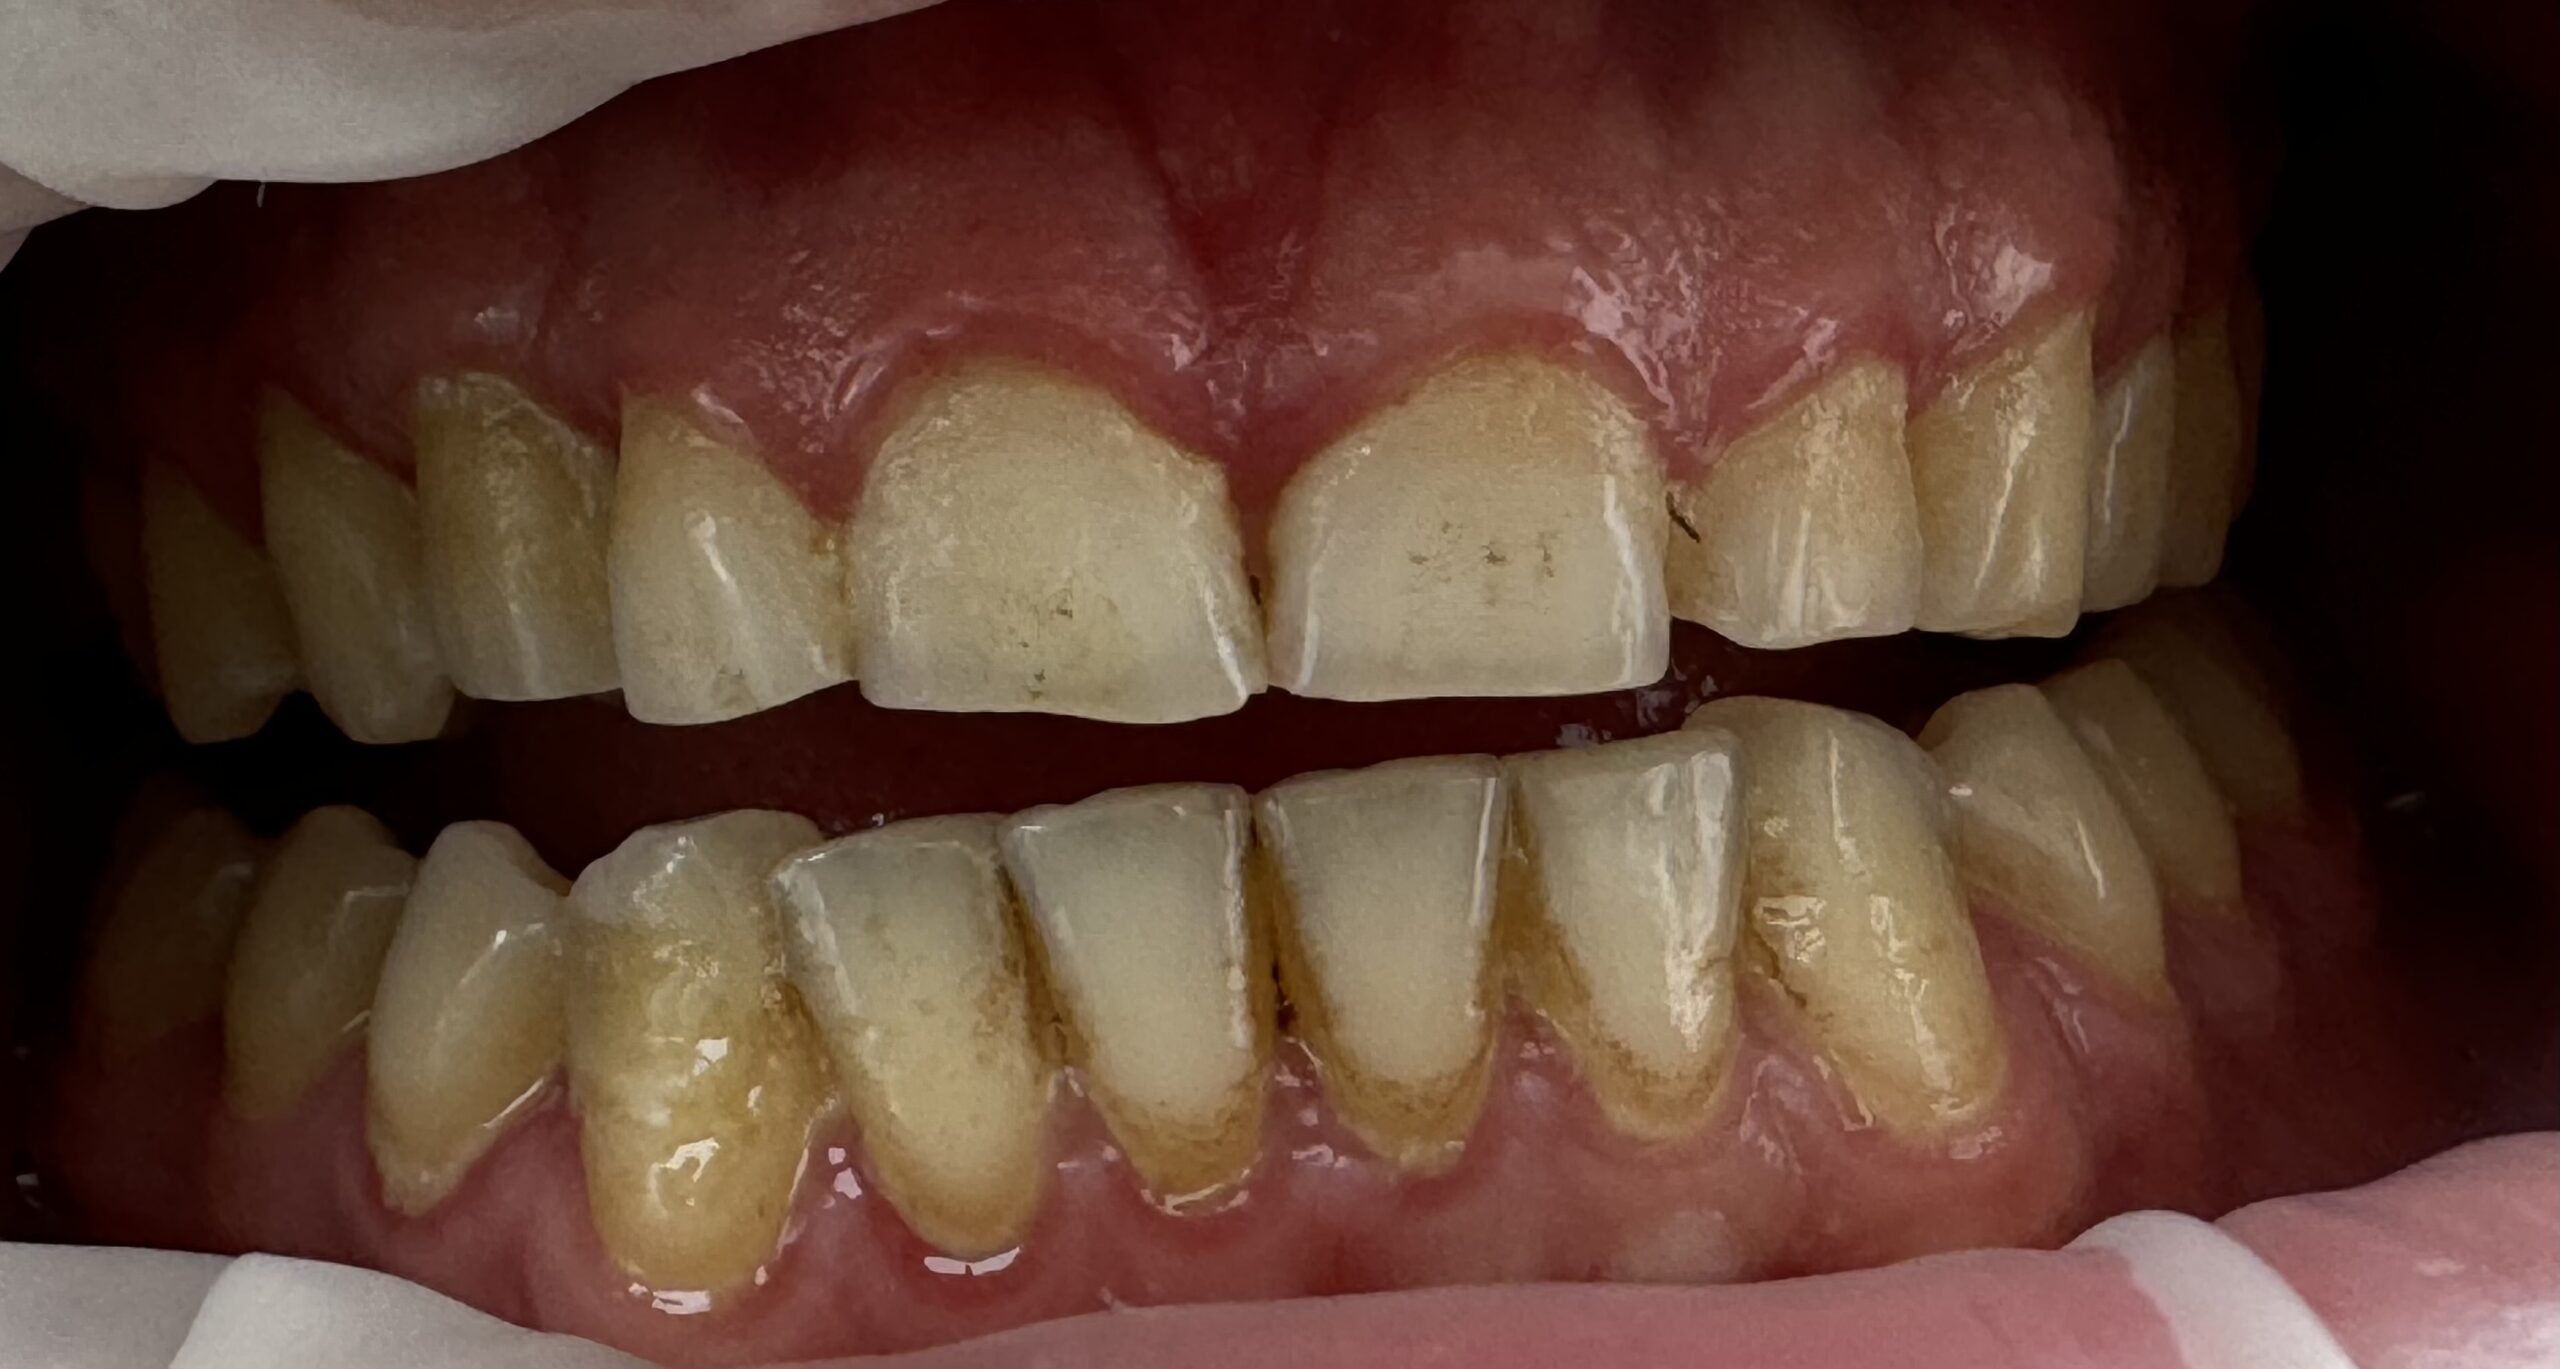

Parodontoza debutează adesea cu gingii roșii, umflate și care sângerează ușor la periaj sau folosirea aței dentare. Pe măsură ce boala progresează, pot apărea retracții gingivale, mobilitate dentară și respirație urât mirositoare. Dacă observi aceste semne, este esențial să consulți un specialist pentru un diagnostic și tratament adecvat.